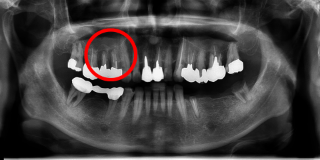

治療前

Xrayから向かって左上の部分の歯を支える骨が溶け、歯がぐらぐらになっている状態を示します。(赤丸の部位)